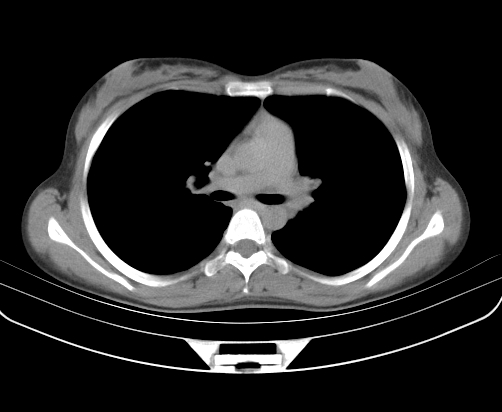

胸部